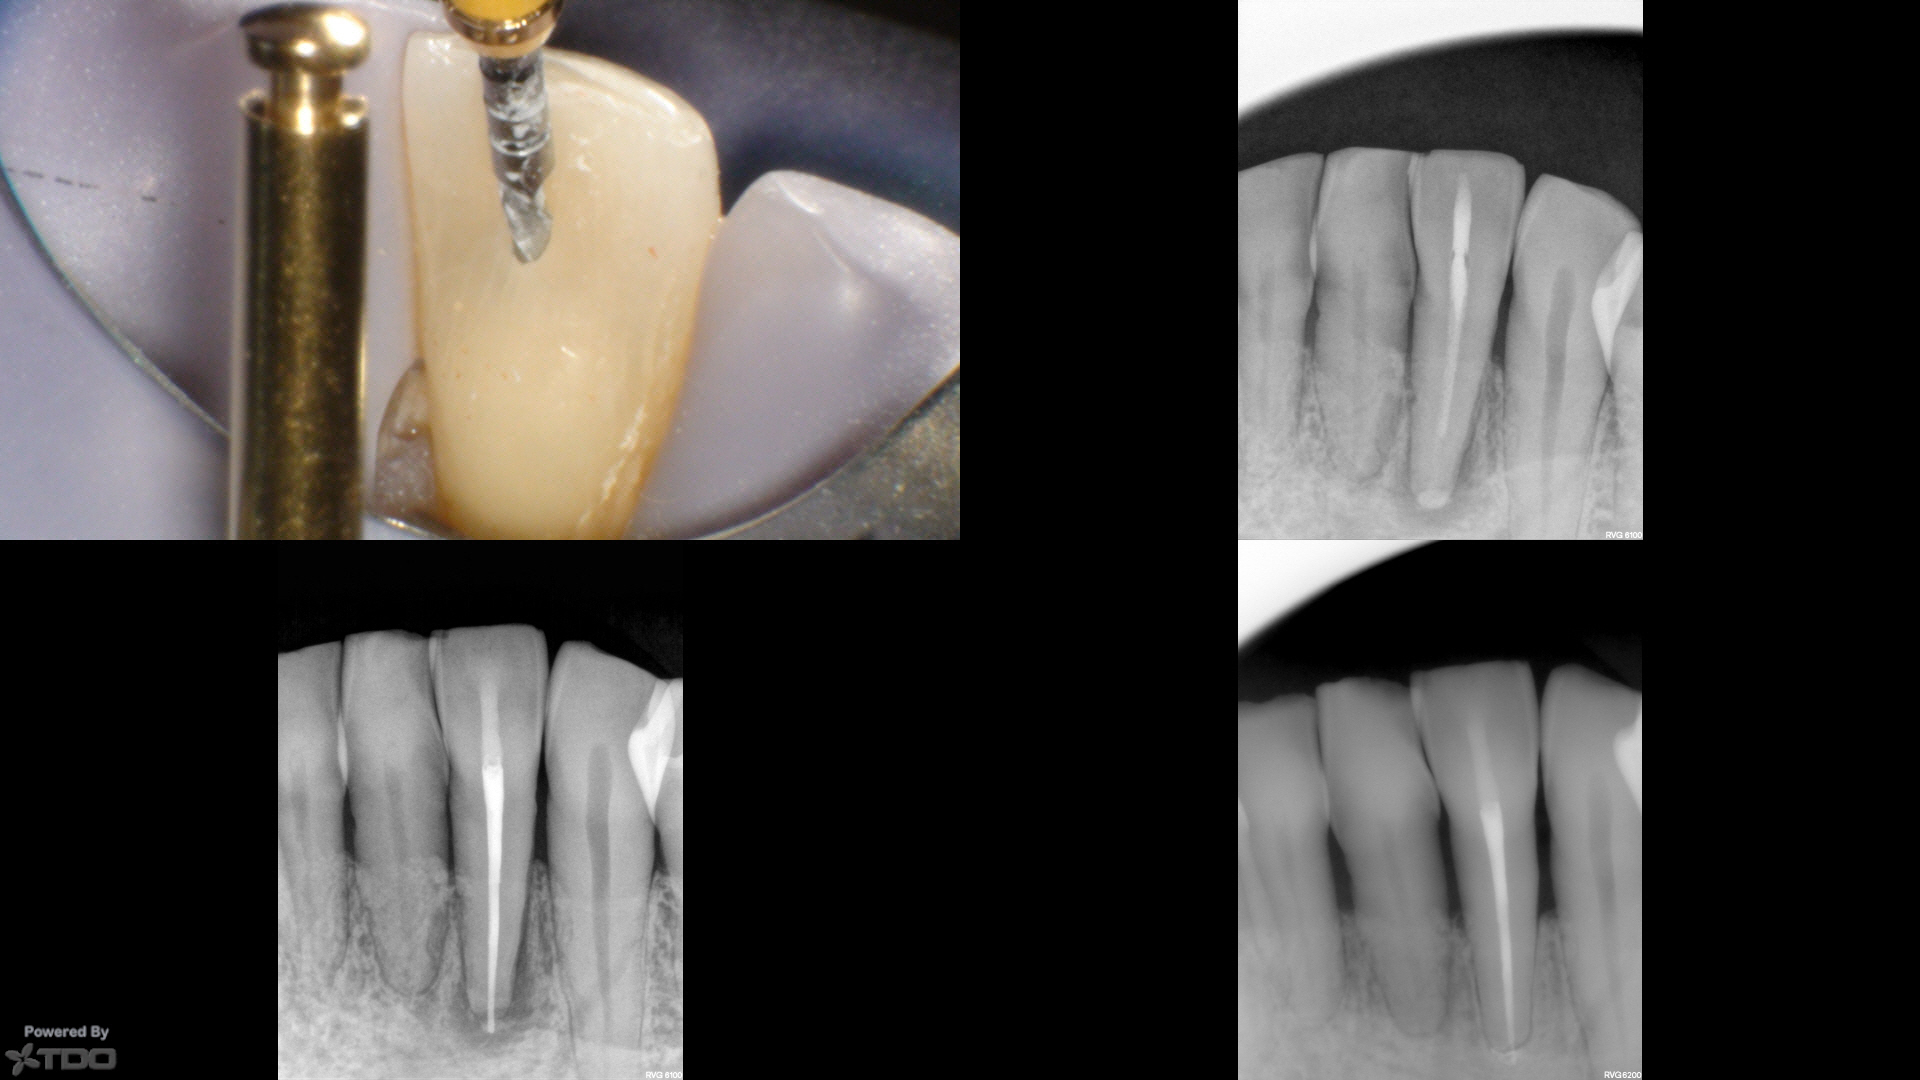

Four year followup.

Look at this case carefully and consider:

What are the chances that this tooth breaks 20 years from now? And since tooth failure on endodontically treated teeth is more related to tooth fracture than endodontic failure—-isn’t this patient far better off with this minimized approach than your typical search and destroy approach?